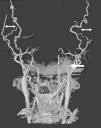

La angiografía computarizada constató en todos los casos la detención del contraste al nivel del agujero magno sin visualizarse contraste en arterias vertebrales intracraneales. Al estudiar la circulación anterior se visualiza un afilamiento progresivo de las arterias carótidas internas en el cuello, comprobándose que el contraste se detiene en la porción petrosa carotídea, y demostrándose la ausencia de relleno de las arterias carótidas internas intracraneales. Se observa relleno de contraste en las diferentes ramas de las arterias carótidas externas (figs. 1-4).

Figura 4. Reconstrucción multiplanar en proyección coronal, que demuestra relleno de contraste de las arterias vertebrales a nivel extracraneal con ausencia de flujo en la fosa posterior.